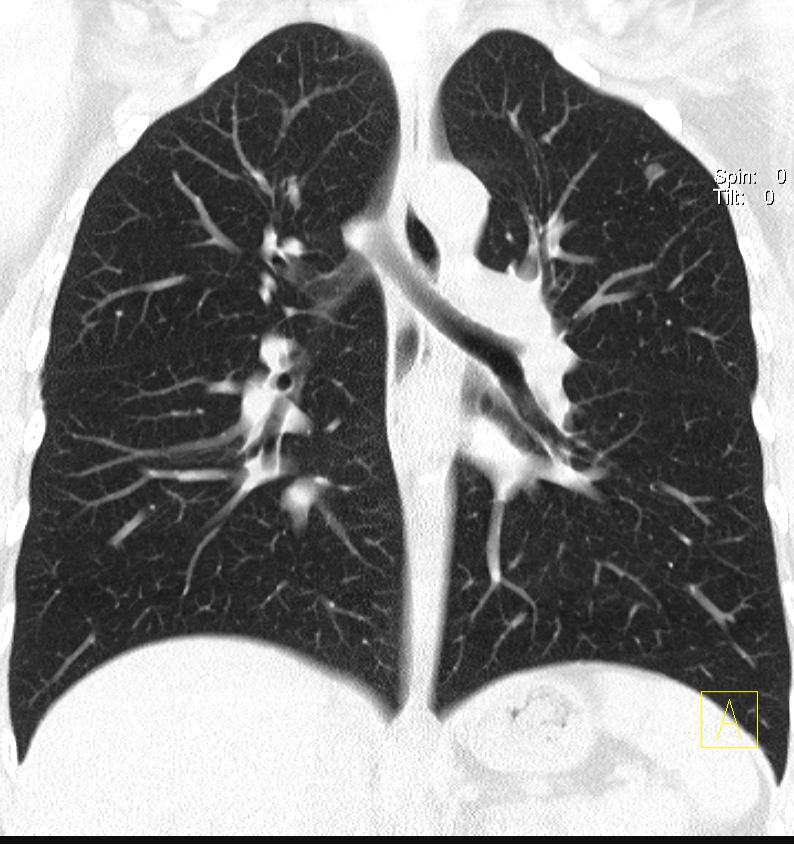

四、呼吸系統(tǒng)成像更精細(xì)

可以完美顯示支氣管樹(shù)、肺血管、肺內(nèi)病灶及相關(guān)毗鄰關(guān)系等,對(duì)支氣管擴(kuò)張、肺氣腫、肺內(nèi)小結(jié)節(jié)、肺癌的診斷等都有獨(dú)特的價(jià)值。